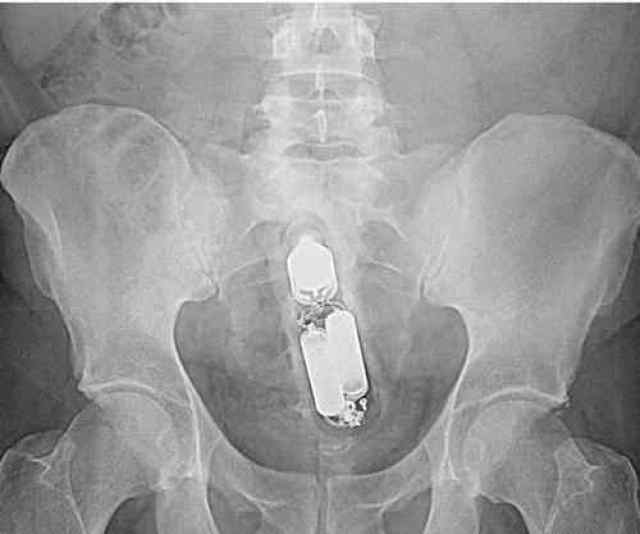

20张x光片,原来玩儿大了啥都可以塞进屁股里.

图片尺寸800x600